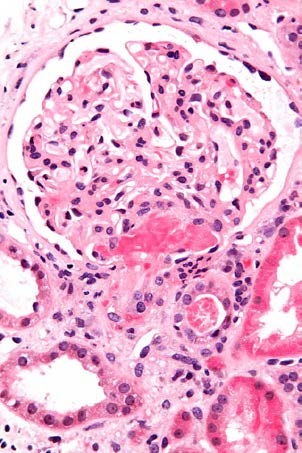

After binding to cell surfaces, Shiga toxin is endocytosed and retrograde-transported to the Golgi apparatus and the endoplasmic reticulum; it is then translocated to the cytosol where it inactivates ribosomes and causes cell death. [18] Micrograph showing an acute thrombotic microangiopathy, as may be seen in TTP. A thrombus is present in the hilum of the glomerulus (center of image). Kidney biopsy. Measurement of ADAMTS13 activity: The value of using information concerning ADAMTS13 for initial diagnosis and treatment decisions remains questionable, especially since such results may not be available for several days, well after initial treatment decisions need to be made. Also, ADAMTS13 activity measured by different methods (eg, using a synthetic substrate versus intact von Willebrand factor) may have discrepant results in some patients.